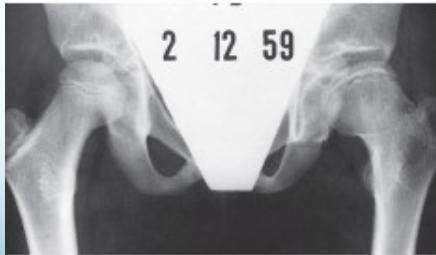

Radiological Progression:

Progression: Sclerosis → Collapse → Fragmentation → Remodeling

Imaging Examples: